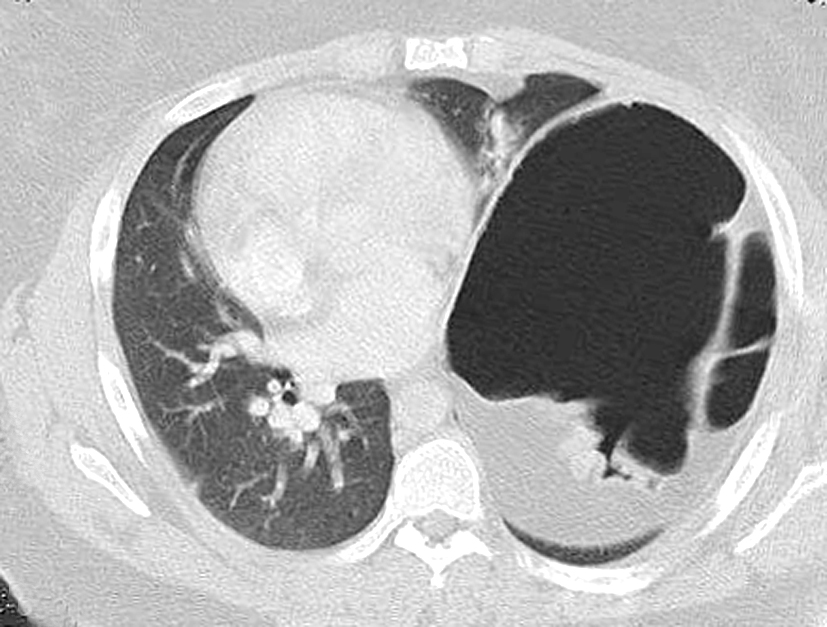

The patient’s postoperative course was uncomplicated and she was discharged on postoperative day 4. She was seen again in the outpatient clinic approximately a week later and a chest x-ray demonstrated a normal left diaphragm contour (Figure 5).